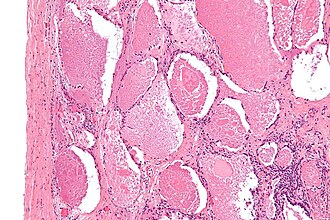

Pulmonary alveolar proteinosis. H&E stain. | |

| LM | "dense bodies" or "chatter" (represent dead macrophages) within acellular eosinophilic material that is in the alveoli |

Microscopic

Features:

- Crap in the alveoli:

- "Dense bodies" - dead macrophages ("Chatter" in the alveoli).

Micro

Sections show lung with eosinophilic material in the airspaces. Focally, small (~20 micrometres), more dense appearing, bodies are also in the airspace. The alveolar walls are within normal limits. No significant inflammation is identified. No microorganisms are seen with routine stains. There is no pulmonary hemorrhage.